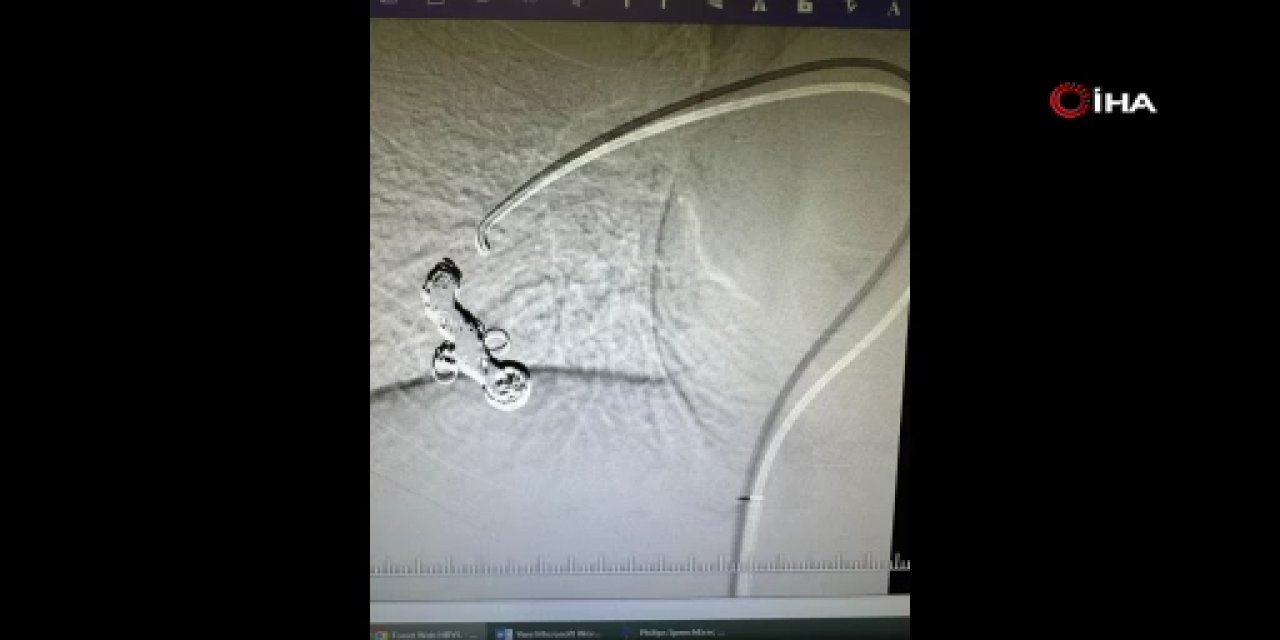

Muğla’da Çocuk Kardiyolojisi Hizmeti Güçlendi: Dr. Ulviye Kırlı Göreve Başladı